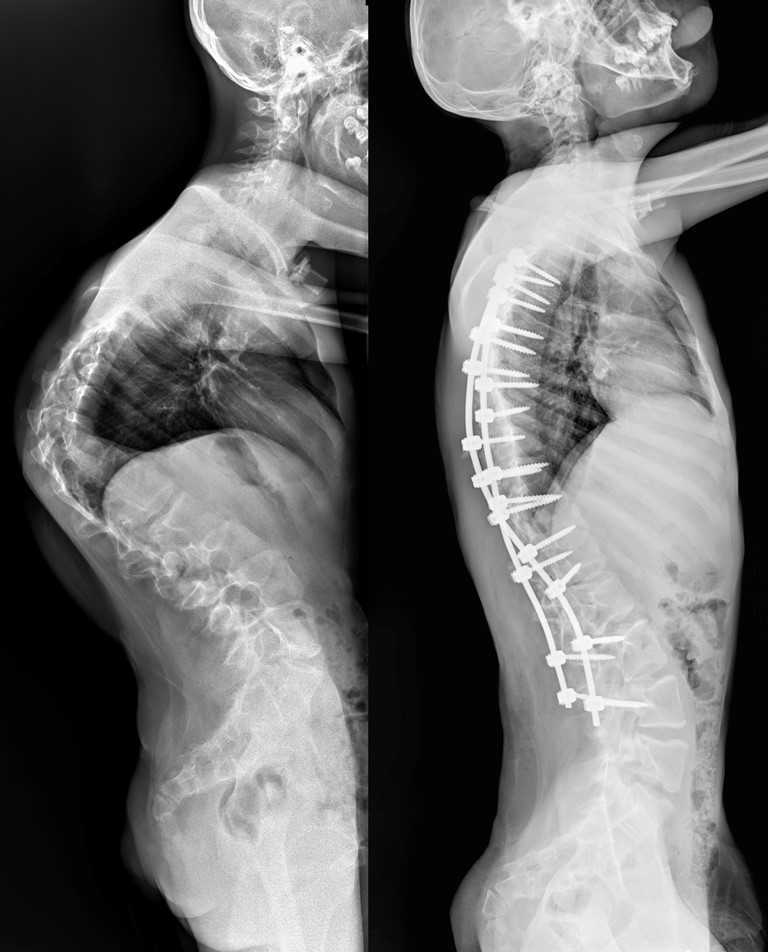

13-летний Мурат страдал от редчайшего генетического заболевания. Врачи провели ему операцию, которая длилась более семи часов. Как отмечают медики, кифотическая деформация грудного отдела позвоночника у юноши составляла более 110 градусов, а комбинированная сколиотическая — по 90 градусов в грудном и поясничном отделах.

В результате операции качество жизни Мурата значительно улучшится. Врачи говорят, что он сможет даже заниматься своим любимым делом — кататься на велосипеде. Болезнь обострилась у юноши около двух лет назад. Он поступил в больницу с существенным искривлением позвоночника.